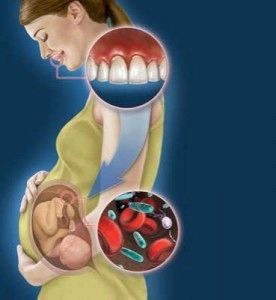

Запалення ясен турбує багатьох людей, а ще воно з завидною періодичністю з'являється у вагітних. Імунітет майбутньої мами ослаблений, адже організму доводиться працювати за двох, тому запалення ясен при вагітності може мати ряд неприємних наслідків при відсутності необхідних заходів.

Через імунодефіциту і інфекційних захворювань запалення ясен у вагітної може перерости в важку форму і привести до утворення мікроскопічних ранок. Зазвичай це відбувається на останньому триместрі вагітності.

Виразкова запалення можна вилікувати тільки за допомогою медикаментозних засобів, тому важливо вчасно діагностувати та усунути гінгівіт. Крім того, у другому триместрі у плода формуються коронки зубів, тому при наявності у матері гінгівіту інфекція може передатися дитині.